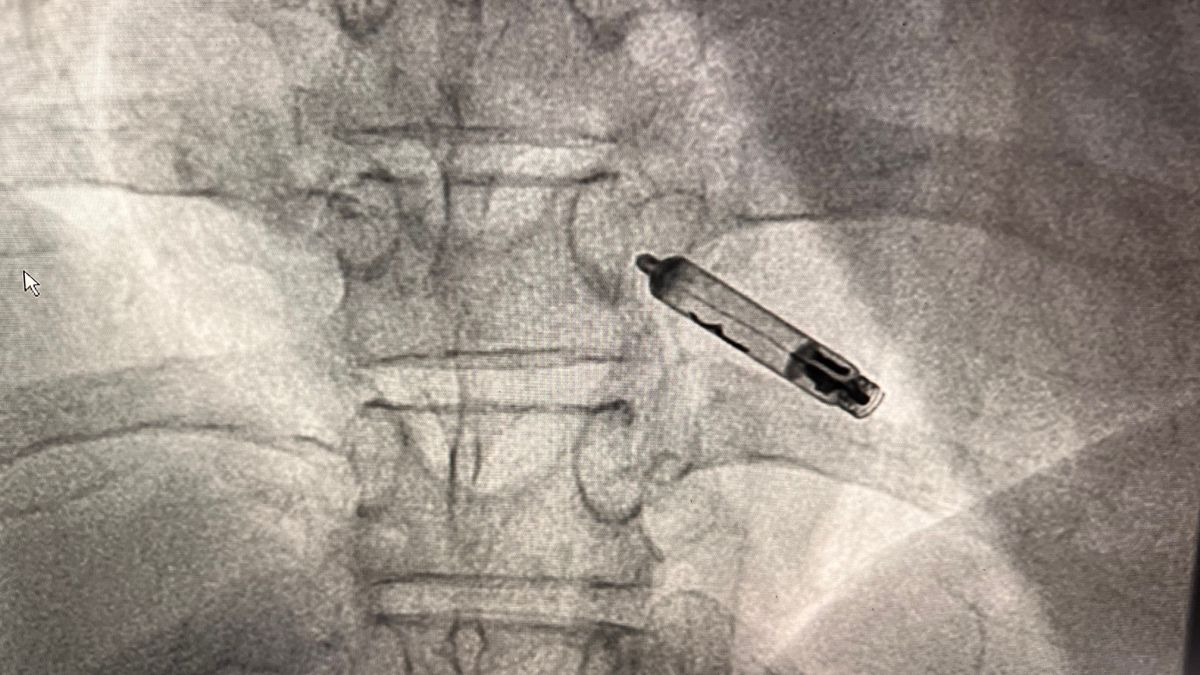

„Der kabellose Schrittmacher ist 3,8 Zentimeter groß, kommt völlig ohne Elektroden aus und wird direkt in die rechte Herzkammer eingesetzt“, erklärt Dr. med. Halit Popi, Oberarzt der Kardiologie der Asklepios Harzkliniken in Goslar. „Der Eingriff erfolgt minimalinvasiv, das heißt über einen kleinen Zugang in der Leiste – ein großer Vorteil für Menschen, bei denen herkömmliche Verfahren zu problematisch oder riskant wären.“

Die neue Technologie stammt vom Hersteller AVIER und kommt speziell dann zum Einsatz, wenn ein klassischer Schrittmacher aus medizinischen Gründen nicht geeignet ist – etwa bei Menschen mit erhöhtem Infektionsrisiko, eingeschränkter Wundheilung, hohem OP-Risiko, onkologischen Vorerkrankungen oder bei Dialysepatientinnen und -patienten. Der „Aveir VR“ ist ein kabelloser Herzschrittmacher, der über eine Vene in der Leistengegend eingebracht und direkt in der rechten Herzkammer verankert wird.